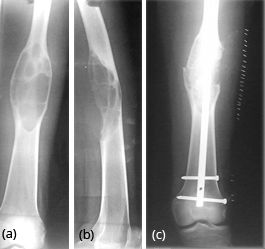

Generally occurs in children less than 10 years. Spontaneous regression is known. Any surgical correction leads to recurrence. Osteofibrous Dysplasia (OD) OD is another entity commonly involving the tibial shaft. Radiologically, an elongated lytic lesion with areas of sclerosis and anterior bowing of the tibia are classical features (Figure 2).

Figure 2a,b: Osteofibrous dysplasia of the tibia. Note the lytic and sclerotic changes scattered. Anterior bowing of the tibia is a characteristic finding.

Shafts of femur, tibia, fibula etc., show expanding lesion with a thick rind. Ground glass appearance of the matrix is the hall mark for diagnosis (Figures 20a,b,c & 21a,b).

Figure 20: FD – (a,b) Mid shaft of femur simulating aneurysmal bone cyst, (c) post operative.